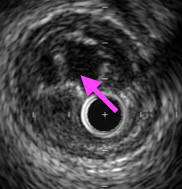

繊維性病変のIVUS画像は、均一で程よく白いプラークなのが特徴だ!

繊維性病変のプラークは安定性が高く、バルーンやステントで拡張しても合併症が少ない。

IVUSで病変を確認し、繊維性病変だったら普段通りPCIを続行しよう。